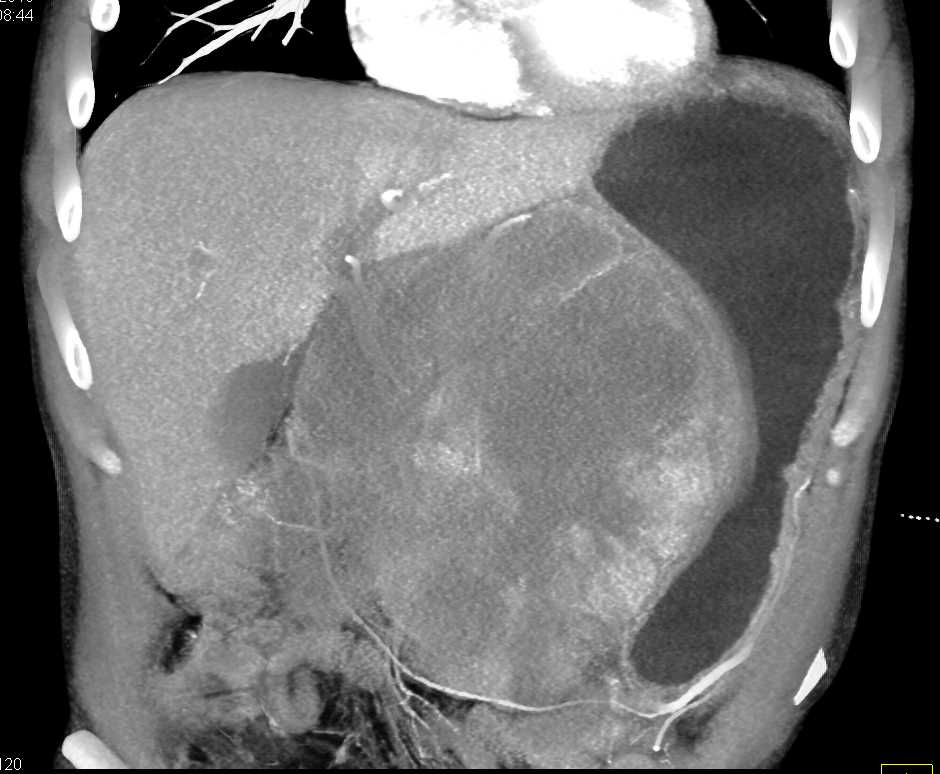

Lagre Gastric GIST Tumor